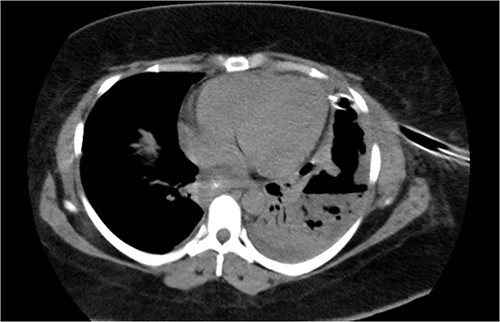

On 19 January 2021, a tomographic control showed leakage from the esophagogastric junction and left-sided pneumonia (Figs 4 and 5). Consultation with the cardiothoracic surgery department led to the decision to perform VATS.

Chest tomography revealing the presence of left pleural fluid and cavitations.

Coronal chest tomography showing the presence of the gastroesophageal stent and the left pleurothoracic cavity.